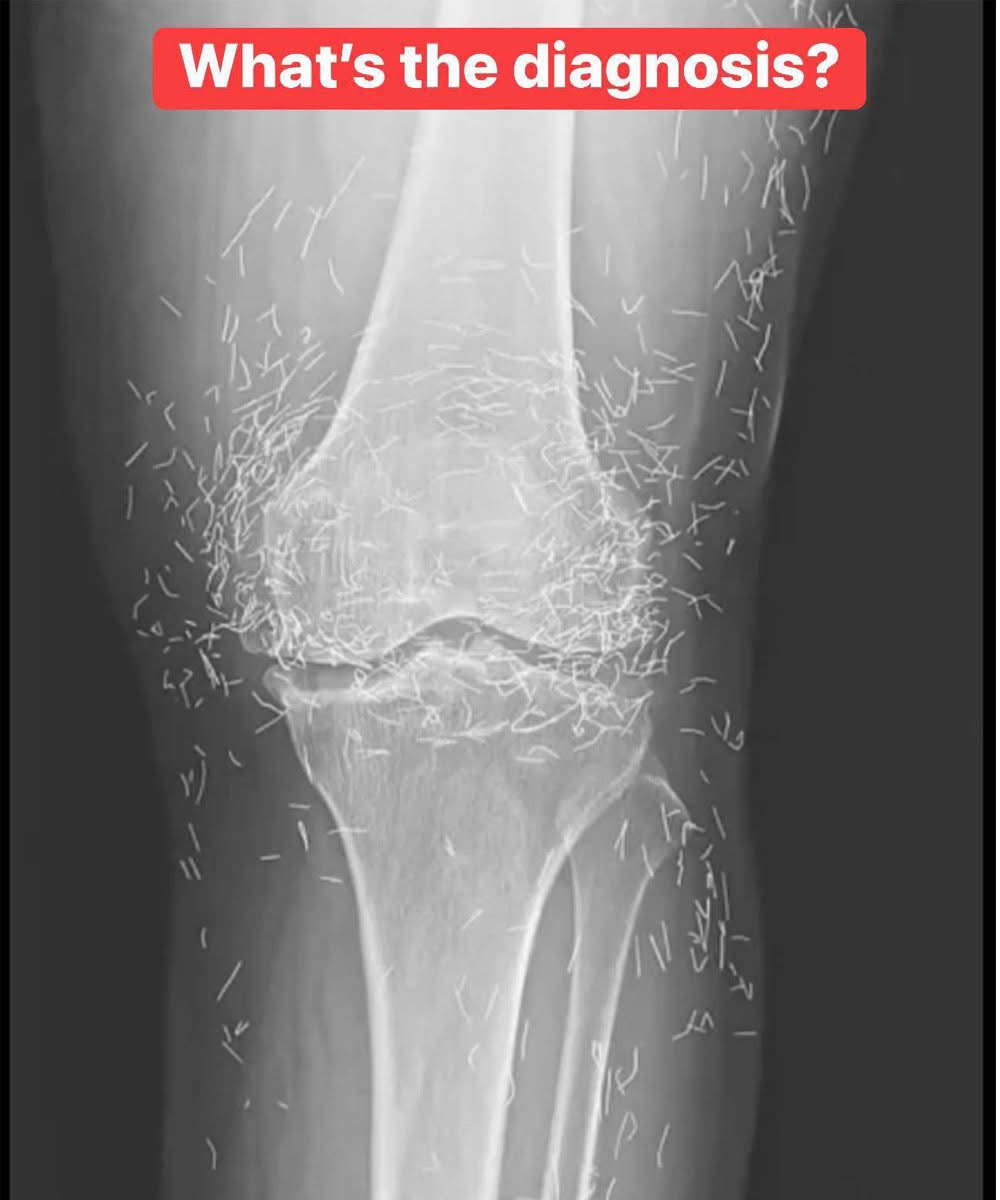

X-Ray Reveals Hundreds of Gold Needles in Woman’s Knees

As doctors examined an X-ray image of the knees of an old woman experiencing severe joint pain, they found a gold mine: hundreds of tiny gold acupuncture needles left in her tissue.

The 65-year-old woman from South Korea had previously been diagnosed with osteoarthritis, a condition in which the cartilage and bones within the joints degrade, causing pain and stiffness. However, when pain relievers and anti-inflammatory drugs didn’t alleviate the pain in her knees and only caused stomach discomfort, she had turned to acupuncture, the doctors wrote last week in the New England Journal of Medicine.

In the woman’s acupuncture treatment, the needles, which were presumably made of gold, were intentionally left in her tissue for continued stimulation, the report says.

Still, leaving the needles, or any objects, in the body may not be such a good idea, according to Dr. Ali Guermazi, a professor of radiology at Boston University, who wasn’t involved with the case. Foreign objects left inside the body can lead to inflammation, abscesses and infection.

It could also make it hard for a doctor to read an X-ray. “The needles may obscure some of the anatomy,” Guermazi said.

Needles left in the body can lead to other challenges, too. “The patient can’t go into an MRI because needles left in the body may move, and damage an artery,” Guermazi said.

Little evidence supports the idea that treating medical conditions with acupuncture actually works. Yet, the practice is widely used as a treatment for painful joints, and the insertion of pieces of sterile gold threads around the joint is a common treatment for arthritis in Asian countries, according to the new report.